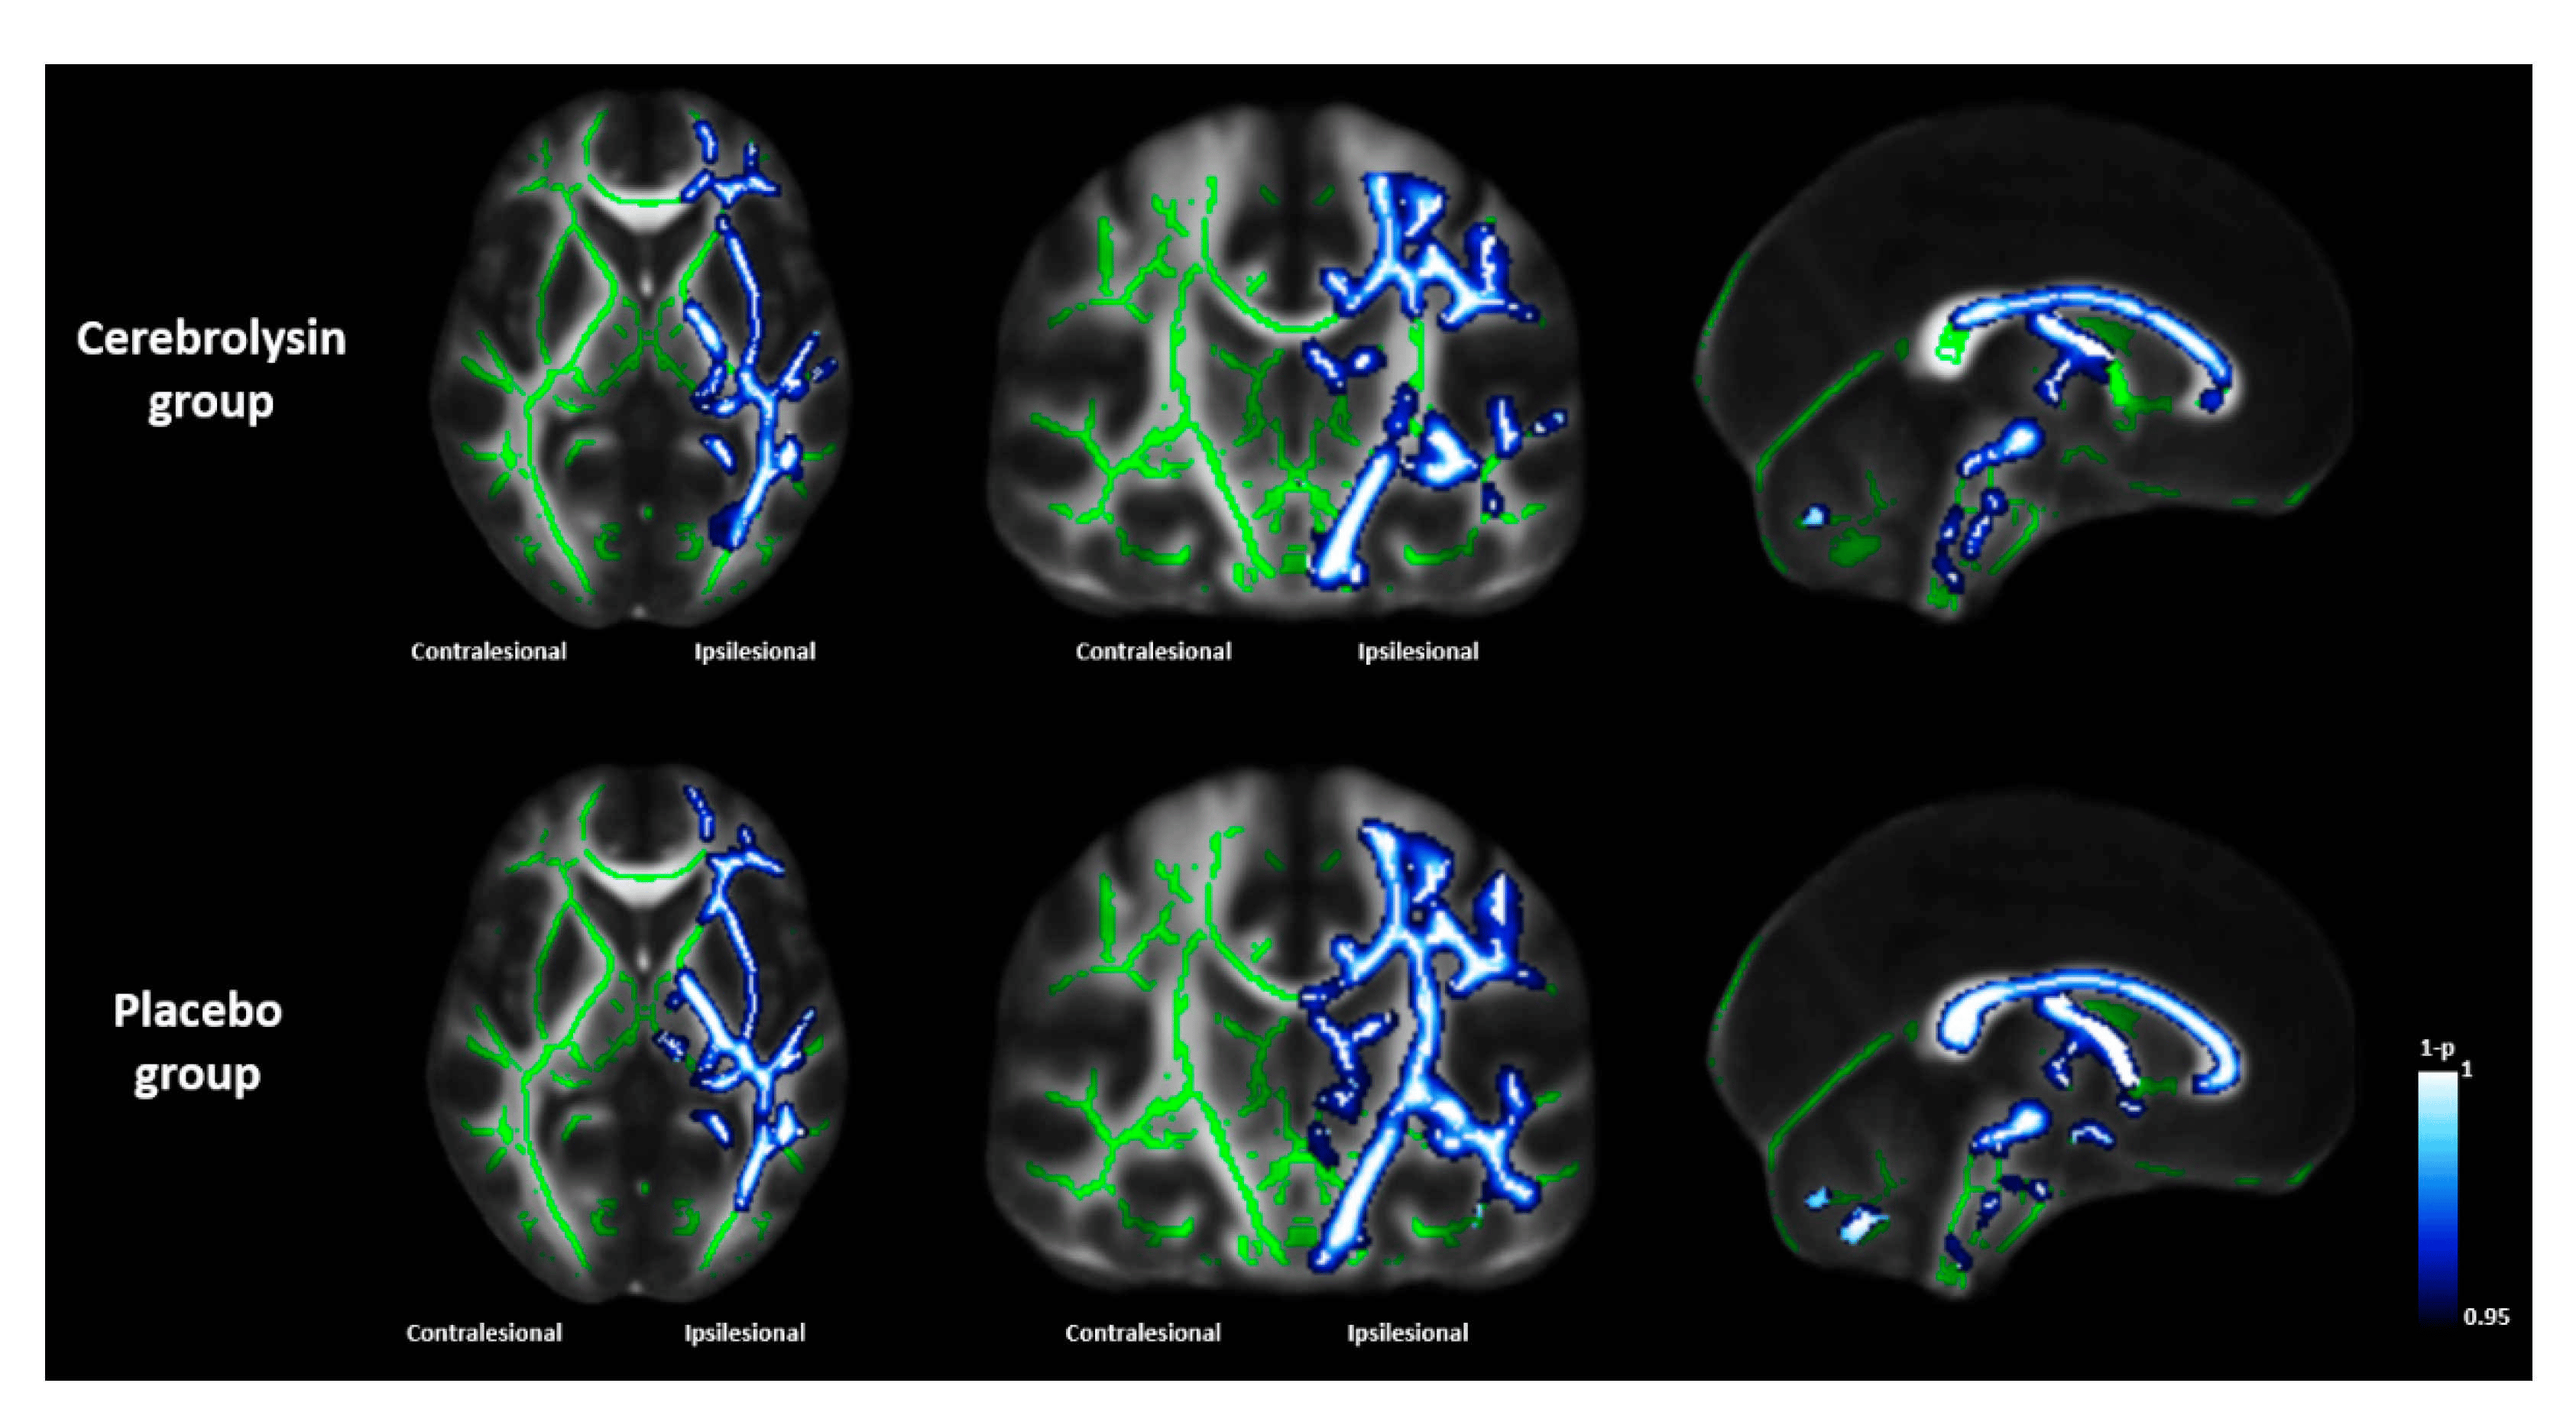

Cerebrolysin has also been used to improve recovery in stroke patients following acute ischemic strokes. Research has shown that it drastically decreases infarct volume (area of dead cells due to oxygen loss) and increases neuron structure integrity [8, 9].